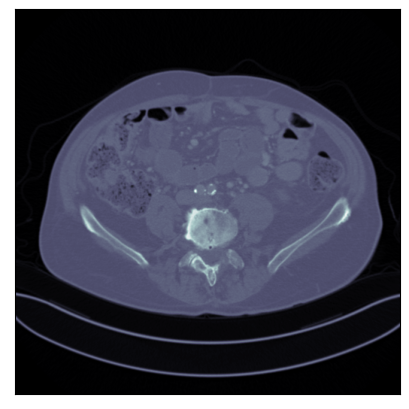

Refer to captionRefer to caption

Ground-truth

FBP: 21.303 dB, 0.195

TV: 31.690 dB, 0.889

U-Net: 36.712 dB, 0.920

LPD: 36.810 dB, 0.912

AR: 36.694 dB, 0.907

ACR: 35.708 dB, 0.897

ACNCR: 36.533 dB, 0.921

AWCR: 37.603 dB, 0.918

AWCR-PD: 37.941 dB, 0.924

Figure 2: Reconstructed images obtained using different methods, along with the associated PSNR and SSIM, for sparse view CT. In this case the AWCR and AWCR-PD achieve the highest PSNR and SSIM. Furthermore, both AWCR methods retain the fine-structure in the reconstruction, unlike the ACNCR and ACR, the only other methods which possess convergence guarantees.

These comparisons illustrate the trade-offs in levels of constraints and supervision versus stability and performance. For details of the experimental set-up, see Section G.1. We measure the performance in terms of the peak signal-to-noise ratio (PSNR) and the structural similarity index (SSIM) [Wang et al., 2004]. We report average test dataset results in Table 1, with further visual examples in Figure 2.

Limited view CT In this setting a specific angular region contains no measurement, turning this into a severely ill-posed inverse problem, and a good image prior is crucial for reconstruction. As shown in [Mukherjee et al., 2021], the AR begins introducing artifacts during reconstruction, which is overcome for both the ACNCR and ACR due to the imposed convexity. The AWCR, on the other hand, is able to remain non-convex without experiencing deterioration. However, the AWCR-PD method performs worse in this setting, though still outperforming AR. This occurs due to the forward and the adjoint operator being severely ill-posed. For a visual comparison of the AWCR and AWCR-PD methods in this setting, see Section G.2.